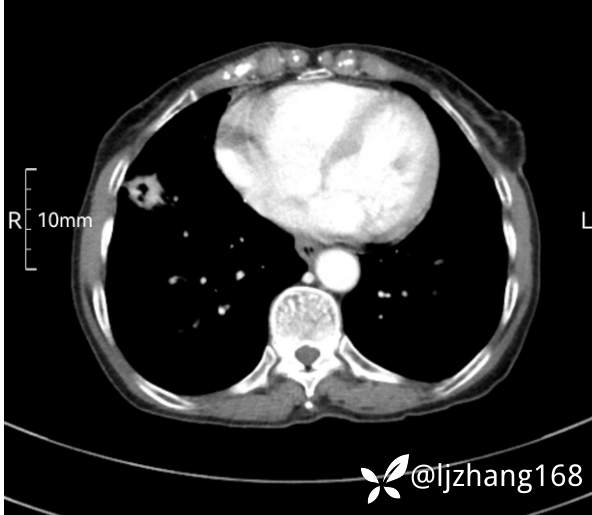

74岁女患,反复咳嗽2月,右肺空洞性病变,炎症OR肿瘤(有病理)

简要病史:2月前开始受凉后出现咳嗽,咳少许白色粘液痰,痰不易咳出,无痰中带血及咯血,无畏寒发热,外院胸部CT提示右下肺空洞病变,脓肿可能性大,常规抗感染治疗效果不佳。既往否认“糖尿病”等病史,有高血压基础病史,无吸烟史。

辅助检查:胸部CT右肺下叶前基底段结节并空洞

临床诊断:右肺空洞:脓肿?